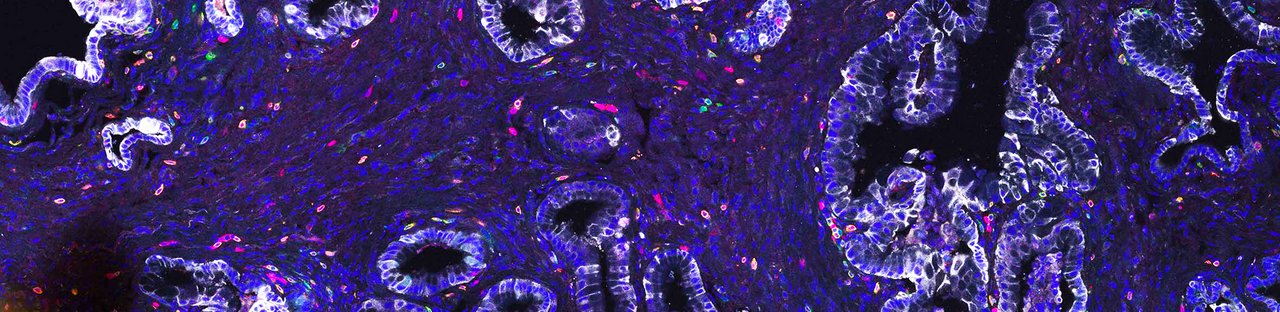

Next, we investigated treatment-induced changes in cell types composing the TME. One of the strongest differences we observed across subtypes and treatment conditions was a remarkable change in T cell composition. Treatment with T/N strongly increased the infiltration of activated CD8+ T cells into mesenchymal tumors. Classical tumors showed treatment induced senescence-associated-secretory-phenotype, recently connected to treatment-induced immune activation. However, in our context they displayed features of immune exclusion – showing only a moderate enrichment of T cells at the tumor margins.

Additional changes were detected in macrophage and neutrophil composition. Notably, in both classical and mesenchymal subtypes, we did not observe a strong change in the number of macrophages, rather in their polarization state: they changed from being mostly pro-tumorigenic M2- to an anti-tumorigenic M1-like state. Moreover, uniquely to classical tumors we observed an increase in neutrophil recruitment upon treatment.

To systematically analyze therapy-induced TME reprogramming, we performed single cell RNA sequencing of both classical and mesenchymal tumors. First, we analyzed treatment-induced changes in the tumor cells of both subtypes. Gene set enrichment analysis revealed treatment-induced DNA-damage, which has been previously shown to activate immune responses. Further, we could see induction of antigen processing and cross-presentation, accompanied by an exclusive and striking enrichment for interferon signaling signatures in mesenchymal PDAC. Next, we focused on the TME and the T cell compartment. T/N treated tumors presented a strong increase in T cells with functional cytotoxic and effector T cell gene expression signatures. The addition of anti-PD-L1 resulted in a further increase of cytotoxic and effector T cells within these tumors. In contrast, classical tumors displayed a decrease of regulatory T cells.